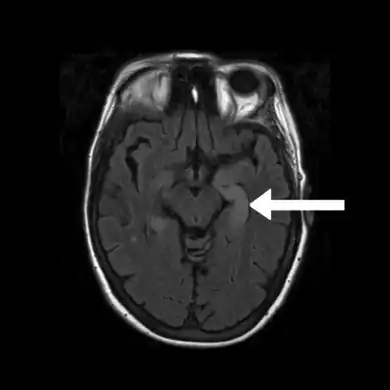

Brain MRI is the mainstay of initial investigation pointing to limbic lobe pathology revealing increased T2 signal involving one or both temporal lobes in most cases.[22][14]

Serial MRI in LE starts as an acute disease with uni- or bilateral swollen temporomesial structures that are hyperintense on fluid attenuation inversion recovery and T2-weighted sequences. Swelling and hyperintensity may persist over months to years, but in most cases progressive temporomesial atrophy develops.[23]